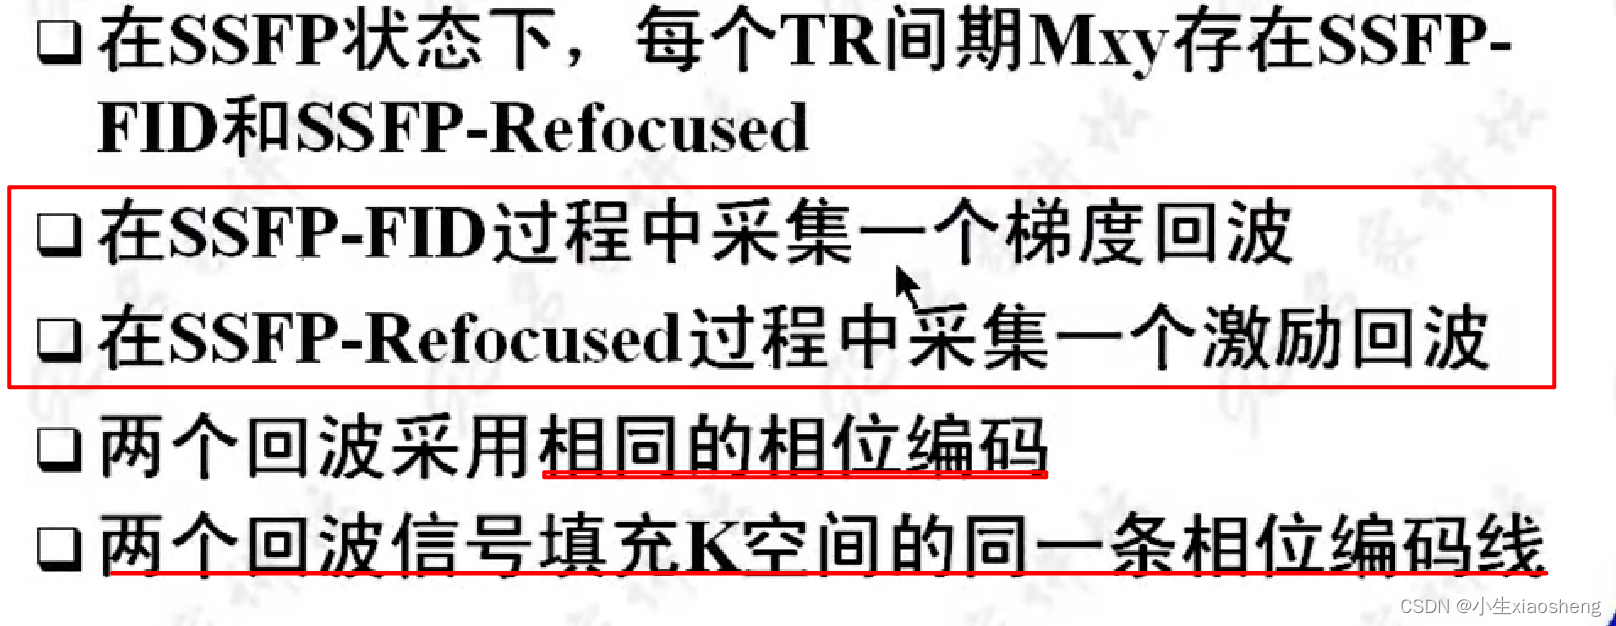

第一次参数的横向脉冲没有全部恢复过来,当第二次脉冲过来时会存在聚焦使得整个脉冲变大,而这个变大的就是SSFP-REF指的是稳态自由进动(Steady-State Free Precession, SSFP)序列中的参考回波(Reference Echo),正常横向的脉冲就叫SSFP-FID。

6.采集双回波的SSFP序列

它在每个TR(重复时间)周期内采集两个回波信号,通常称为“双激发”或“双回波”技术。在SSFP序列中,射频脉冲和梯度场被连续应用以产生稳态的进动信号。在双回波SSFP序列中,可以通过调整射频脉冲和梯度场的参数来在每个TR周期内激发并采集两个回波信号。

这两个回波信号可以通过不同的方式来获取和利用。一种常见的方法是使用两个不同的读出梯度场来分别采集两个回波,这两个回波可以具有不同的对比度和分辨率特性。通过这种方式,可以同时获取到关于组织结构的更多信息,提高图像的质量和诊断的准确性。目前也用的少